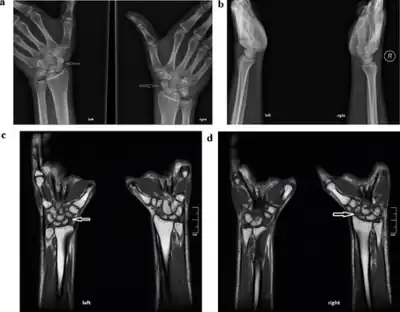

X-rays usually do not show evidence of new stress fractures, but can be used approximately three weeks after onset of pain when the bone begins to remodel.[4] A CT scan, MRI, or 3-phase bone scan may be more effective for early diagnosis.[7]

MRI appears to be the most accurate diagnostic test.[8]